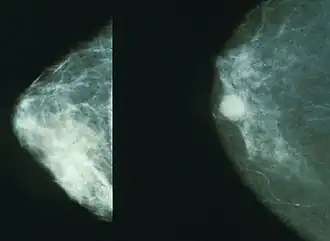

Breasts

Projectional radiography of the breasts is called mammography. This has been used mostly on women to screen for breast cancer, but is also used to view male breasts, and used in conjunction with a radiologist or a surgeon to localise suspicious tissues before a biopsy or a lumpectomy. Breast implants designed to enlarge the breasts reduce the viewing ability of mammography, and require more time for imaging as more views need to be taken. This is because the material used in the implant is very dense compared to breast tissue, and looks white (clear) on the film. The radiation used for mammography tends to be softer (has a lower photon energy) than that used for the harder tissues. Often a tube with a molybdenum anode is used with about 30 000 volts (30 kV), giving a range of X-ray energies of about 15-30 keV. Many of these photons are "characteristic radiation" of a specific energy determined by the atomic structure of the target material (Mo-K radiation).